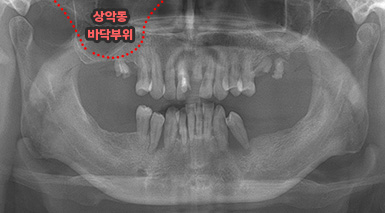

상악동은 윗턱뼈 내부의 구조물로서 개개인에 따라 생김새가 다릅니다.

상악동의 바닥이 잇몸뼈 방향으로 많이 내려온 경우, 임플란트를 식립하기에

잇몸뼈가 부족하게 됩니다. 이러한 경우 상악동 내부로 뼈이식을 하는

상악동 거상술이 필요하게 됩니다.